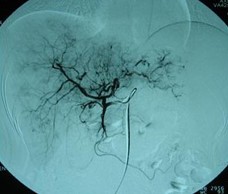

患者情况:肝细胞性肝癌,术后复发,右肝内多个病灶。治疗方案:瘤内注射今又生1×1012VP/次/周,共8周,同时联合肝动脉化疗栓塞(TACE),1次/月,共2次。下图示:左侧上下两图为治疗前,CT示血管丰富;右侧上下两图为治疗一个疗程后,碘油均匀沉积,肿瘤血供减少。